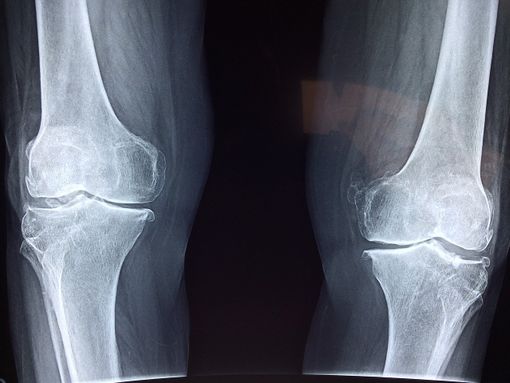

L'osteoartrosi è una malattia reumatologica degenerativa caratterizzata dal danneggiamento progressivo della cartilagine. È un disturbo abbastanza comune che colpisce più donne che uomini.

I suoi sintomi principali si manifestano sotto forma di rigidità articolare, dolore o deformazione delle ossa. Si tratta quindi di una patologia che causa dolore e che, nei casi più gravi, può causare problemi di mobilità nel paziente. Tant'è che secondo la Guida Clinica prodotta dal Ministero della Salute del Cile (Minsal), l'artrosi è la prima causa di deterioramento della mobilità nelle donne.

La verità è che la causa esatta per cui si manifesta l'osteoartrosi non è nota. Tuttavia, ci sono alcuni fattori associati al suo sviluppo, come la debolezza muscolare o l'eccesso di peso. Nel caso di persone in sovrappeso affette da artrosi, le zone più colpite sono, in generale, le ginocchia e le anche.